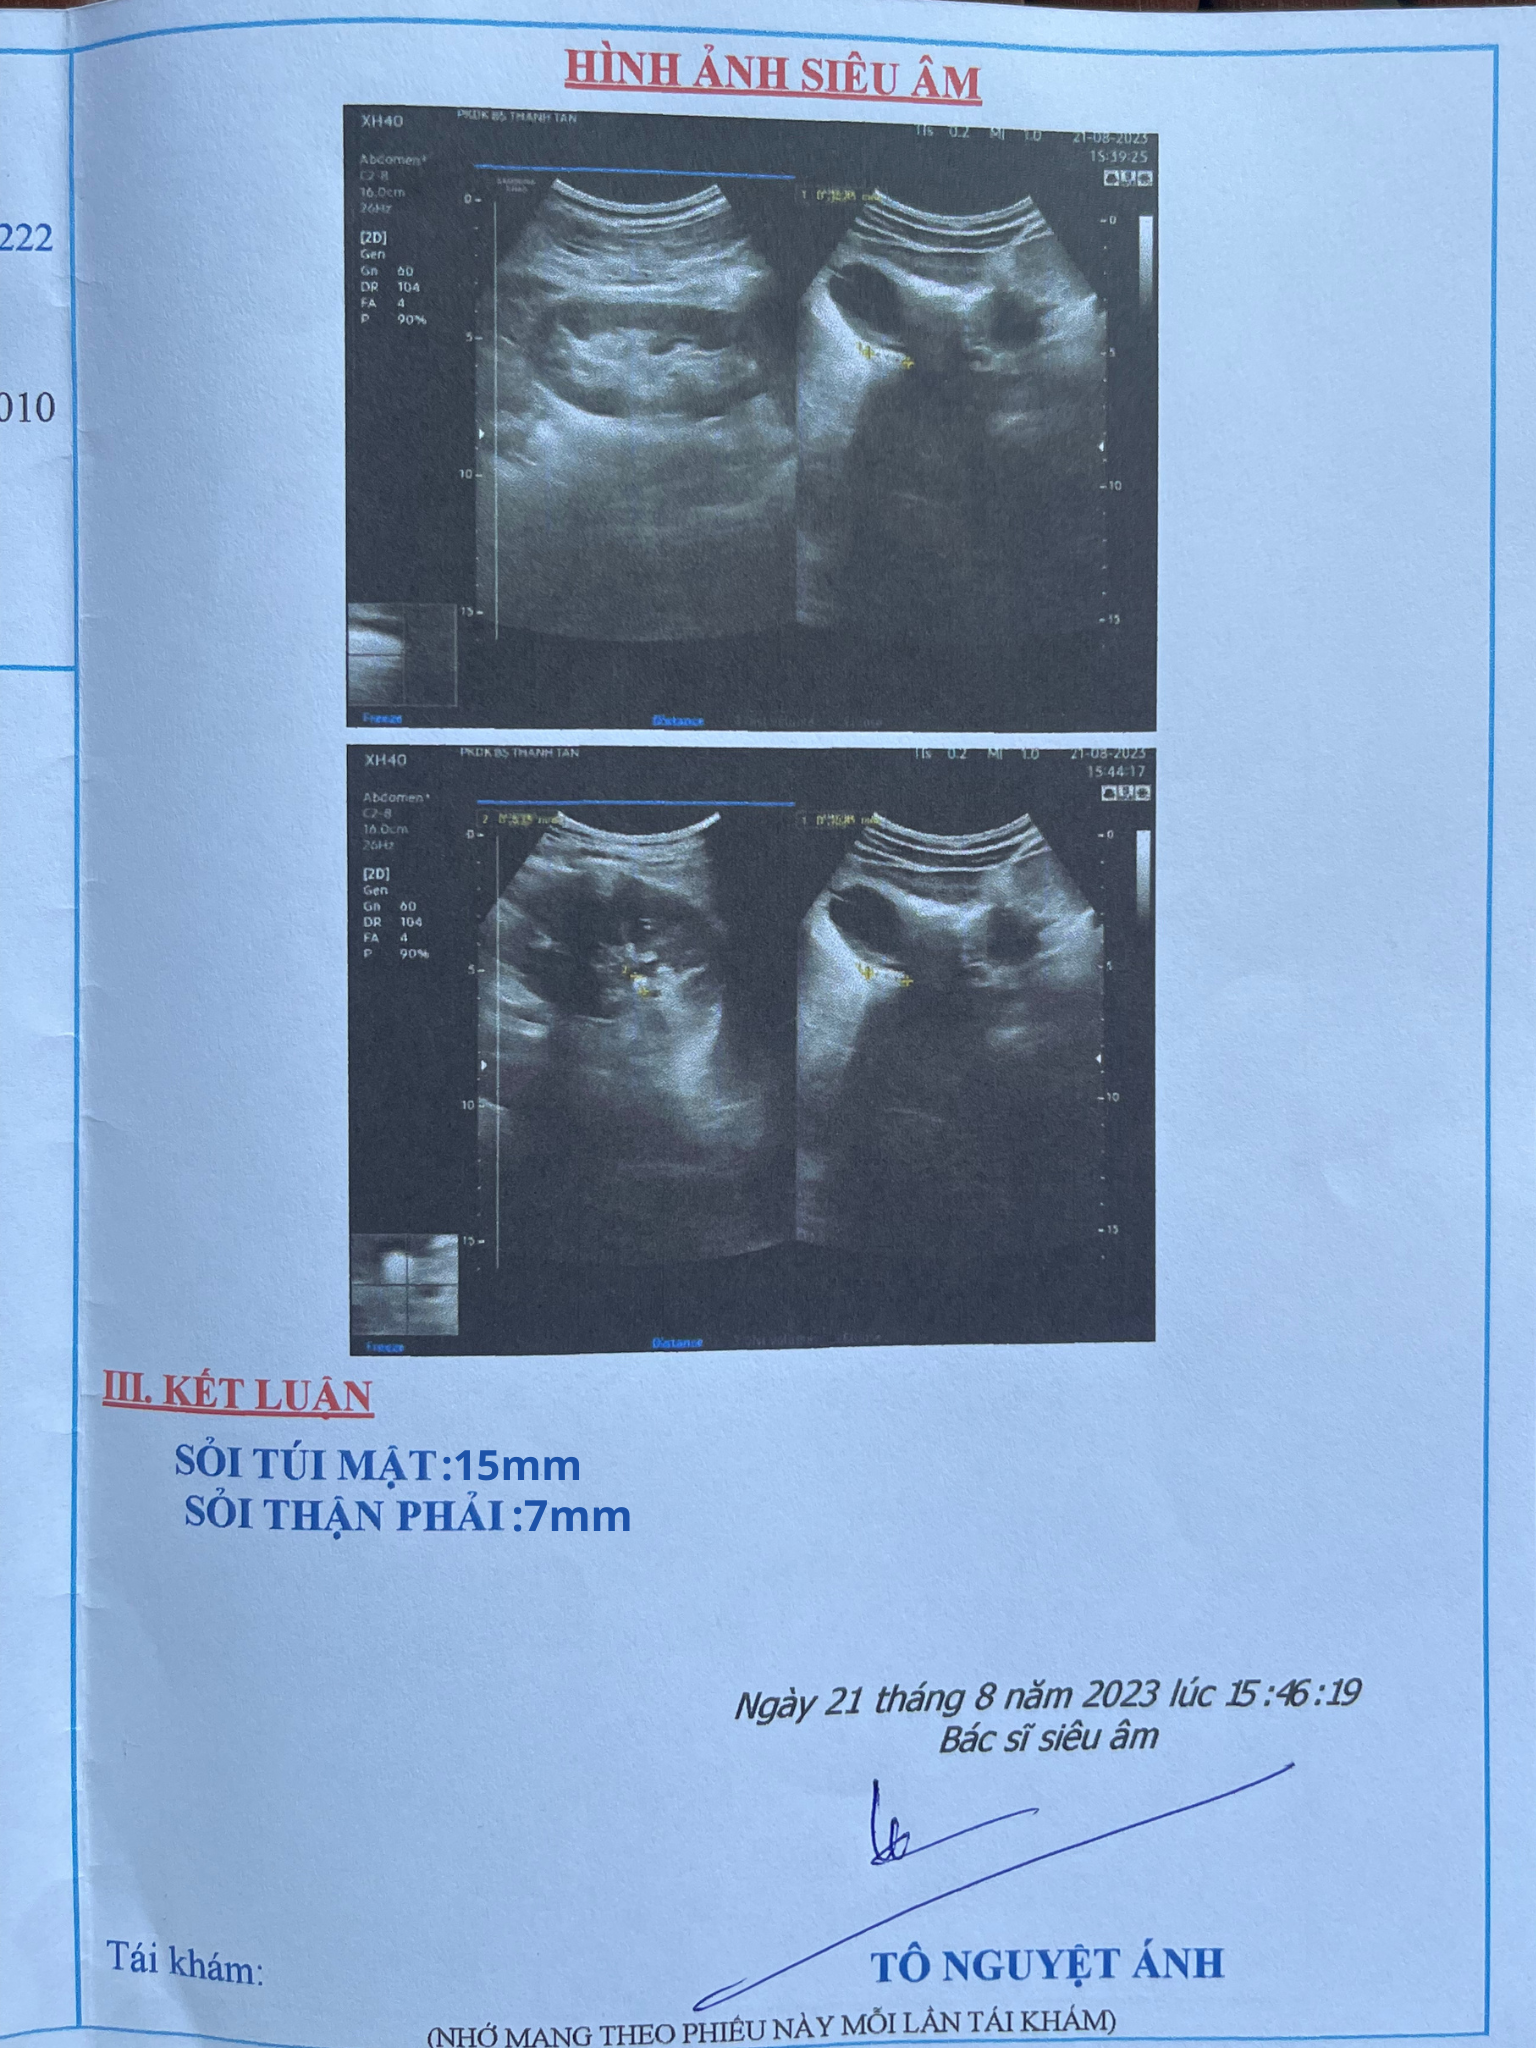

“Đau quá không chịu được tôi đi khám tại bệnh viện đa khoa Gò Dầu, bác sĩ chẩn đoán tôi mắc sỏi túi mật 15mm và sỏi thận 7mm. Sỏi kích thước lớn nên bác sĩ khuyên tôi nên sớm phẫu thuật cắt túi mật.

Chú Văn Anh bất ngờ phát hiện ra sỏi túi mật 15mm khi kích thước đã lớn